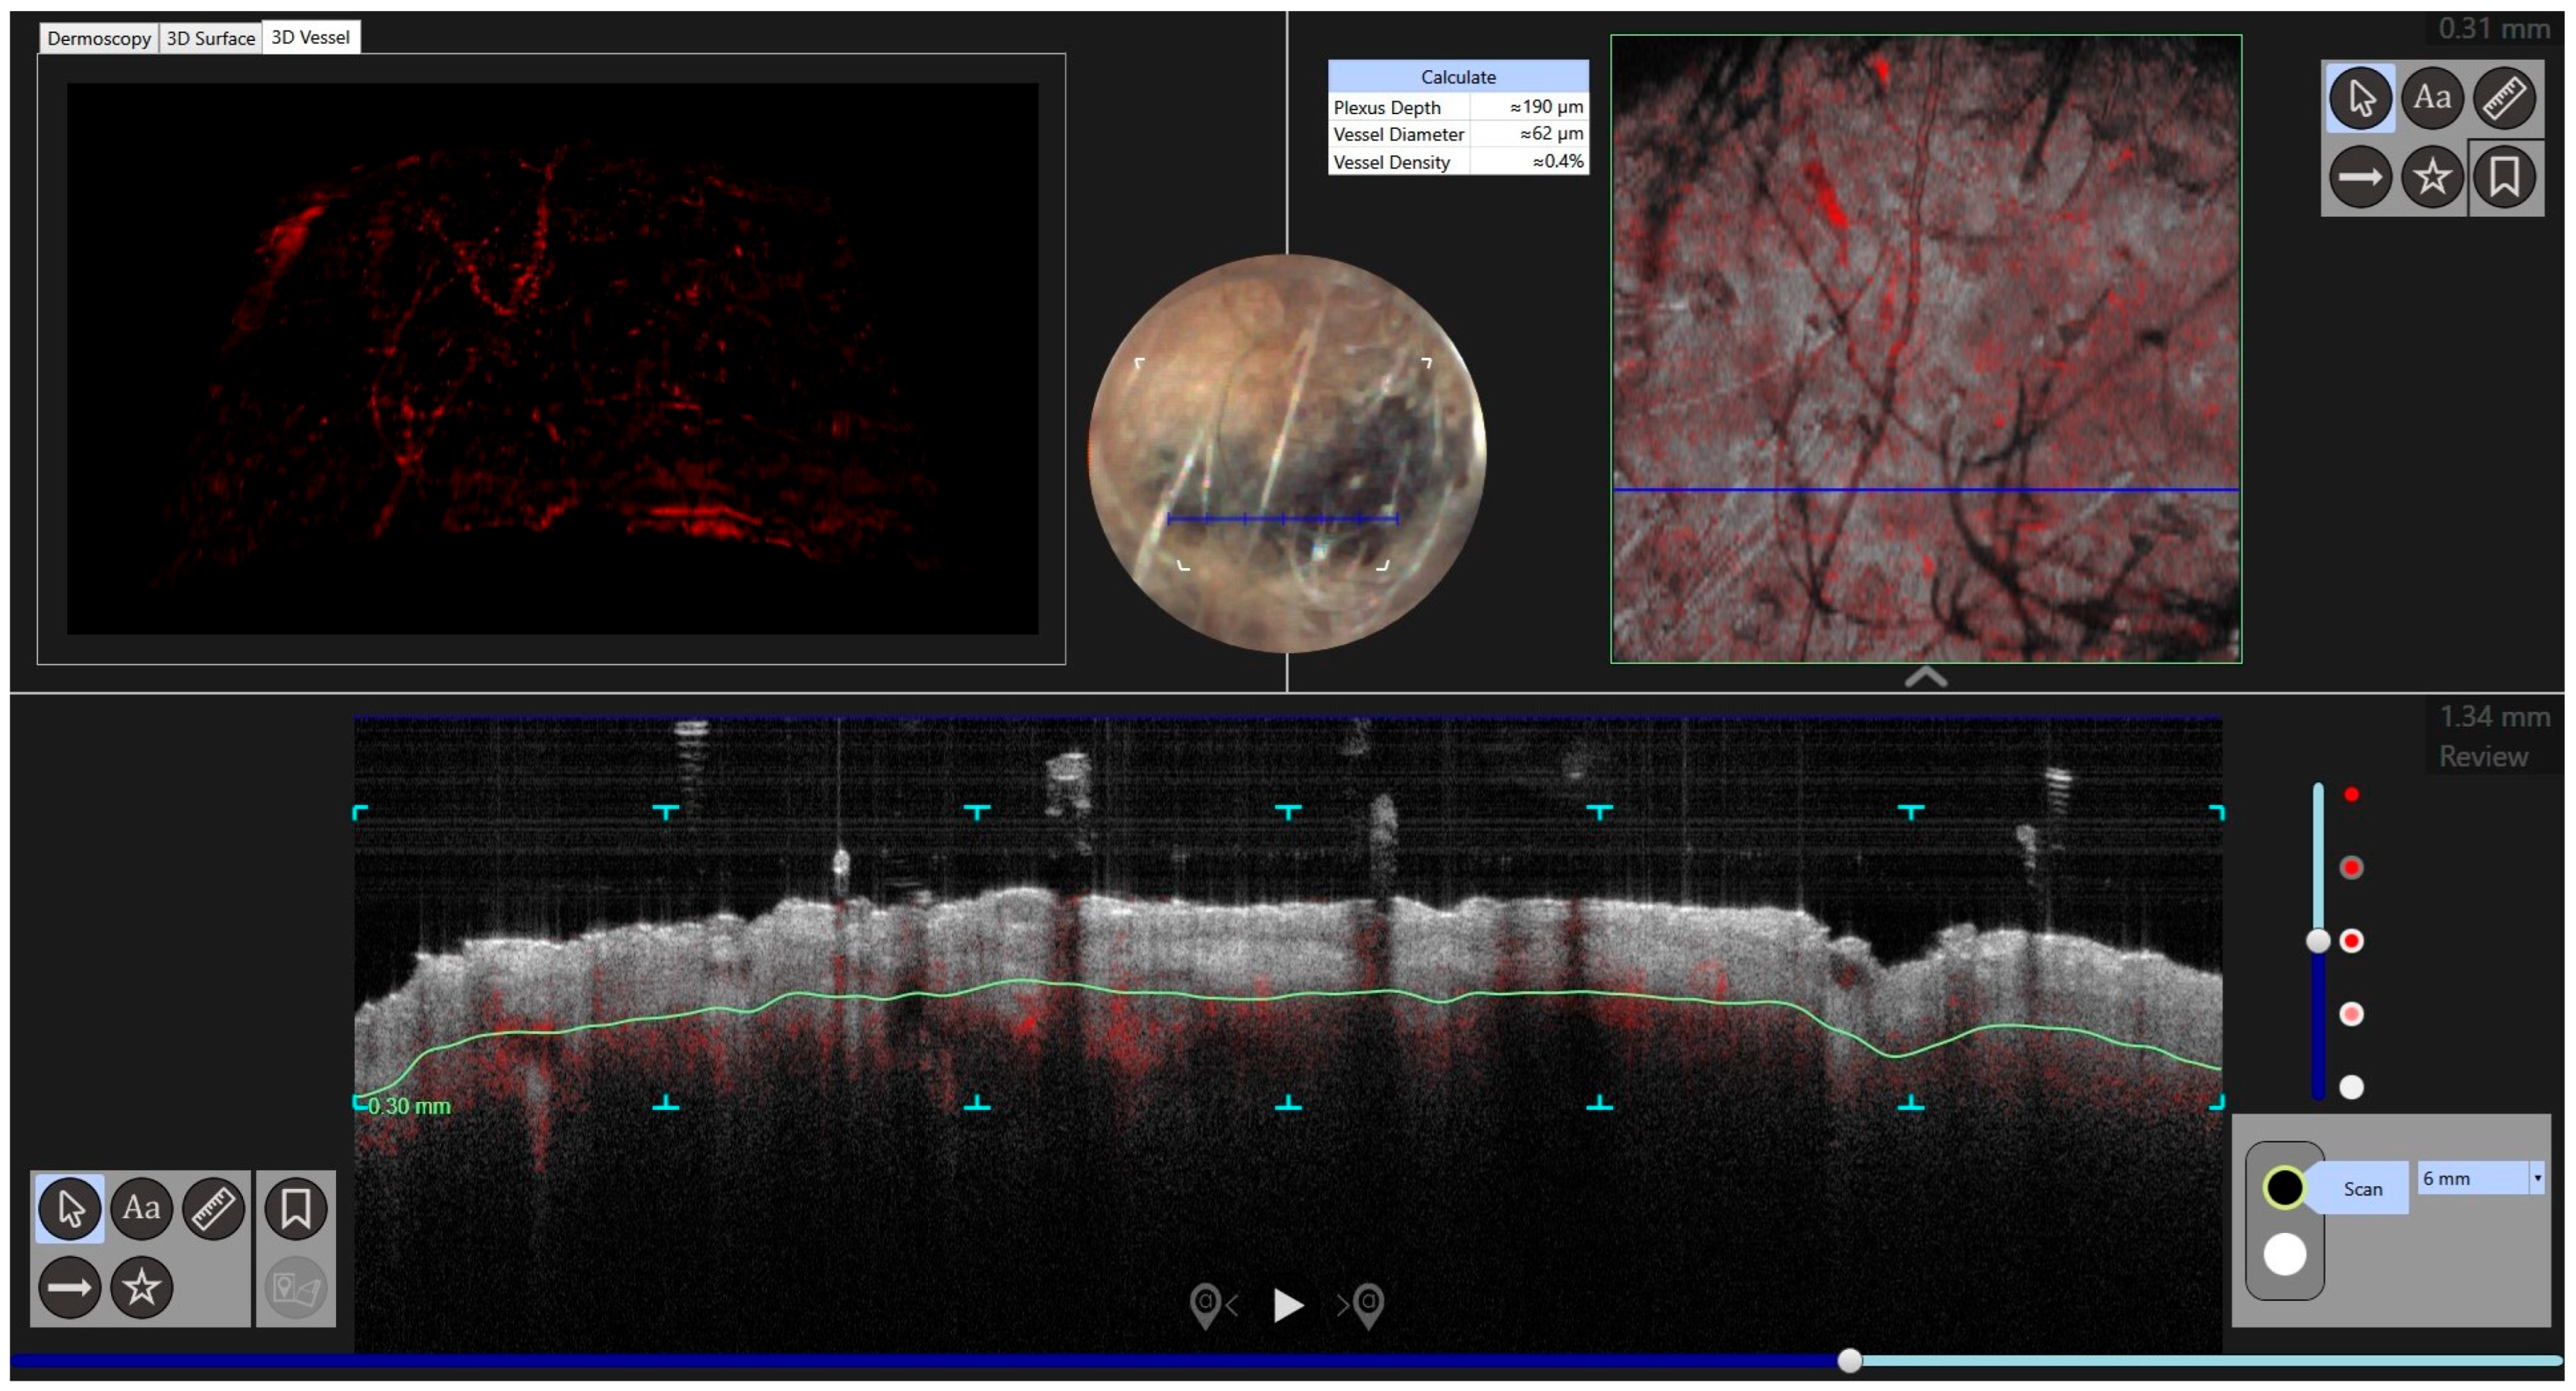

| Case | Age in Years/Gender | Clinical Morphology | Dermoscopic Features | Histology |

|---|---|---|---|---|

| 1 | 53/M | Blue–black plaque with multiple bluish papules and macules | Homogenous blue–gray pattern with yellow hue | Locally advanced melanoma |

| 2 | 86/M | Blue–black plaque with multiple blue satellitosis | Homogenous blue–gray pattern | Metastatic melanoma |

| 3 | 38/F | Blue nodule with agminated pigmentated macules | Homogenous violet-blue pattern with serpentine vessels | Desmoplastic blue nevus |

| 4 | 77/F | Blue–black macule and interspersed pigmentated lesions of scalp | Homogenous blue–brown pattern | Common blue nevus |